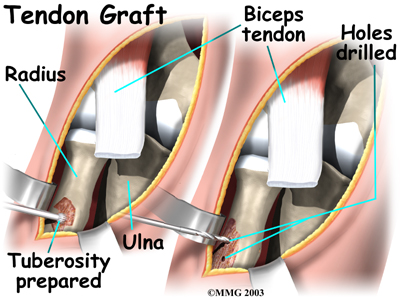

Graft Repair

If more than three or four weeks have passed since the rupture, the surgeon will usually need to make a larger incision in the front of the elbow. Also, because the tendon will have retracted further up the arm, graft tissue will be needed in order to reconnect the biceps to its original point of attachment on the radial tuberosity.

The surgeon begins by making a across the arm, just above the elbow joint. The incision curves along the front surface of the upper arm to expose the lower part of the biceps muscle.

The surface of the is removed. A burr is used to create a small cavity within the tuberosity. Several suture holes are drilled around the rim of the tuberosity.

A curved instrument is passed through the incision and directly between the radius and ulna bones. The surgeon pushes the instrument through this space, puncturing the muscles and soft tissues. The surgeon feels the back of the forearm to find the point where the instrument is protruding. A is made at this spot.

The surgeon then prepares a graft of tissue to lengthen the retracted biceps tendon. Some surgeons use a piece of hamstring tendon for the graft. Others use a section of the Achilles tendon where it attaches to the heel. This type of graft is usually an allograft, meaning that the tissue is taken from a cadaver (human tissue preserved for medical purposes).

When the is used, the surgeon leaves a small piece of the heel bone attached to the piece of tendon. Small holes are drilled into the piece of bone. Sutures are woven through these holes and will later be used to secure the end of the graft to the radial tuberosity. In this way, the graft will have a bone-to-bone connection that heals together. The healed bone solidly fixes the the graft to the radial tuberosity. After the graft is in place, its top end is then stitched over the front of the biceps muscle.

Next, the lower end of the graft is passed between the radius and ulna, exiting through the second incision that was made on the back of the forearm. The sutures from the bony end of the graft are threaded into holes that were drilled into the rim of the radial tuberosity earlier. The surgeon ties the sutures, to the radius.

When the surgeon is satisfied with the repair, the skin incisions are closed, and the elbow is placed in a protective brace.